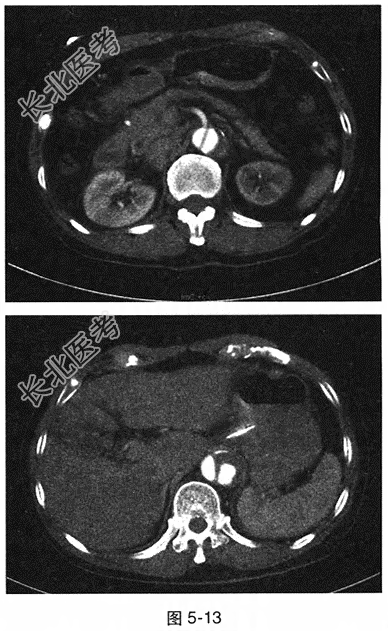

- 多项选择题2.[提示]ECG:窦性心律, HR38次/min,Ⅱ、Ⅲ、aVF导联ST段压低0.1mV。实验室检查: 外周血WBC 13.7×10⁹/L,N 0.873; ALT 180U/L,AST 146U/L, 白蛋白28.0g/L,血淀粉酶165U/L, 脂肪酶1117.0U/L。腹部增强CT见图5-13。

- 多项选择题3.[提示]腹部CT显示:主动脉内散在低密度血栓影, 可见内膜钙化内移,初始破口位于升主动脉, 范围累及胸主动脉至腹主动脉分叉处。 该患者的类型为